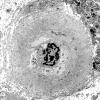

PERIPHERAL NEUROPATHY

11 VASCULITIS - VASCULOPATHY

2 Vasculopathy (3)